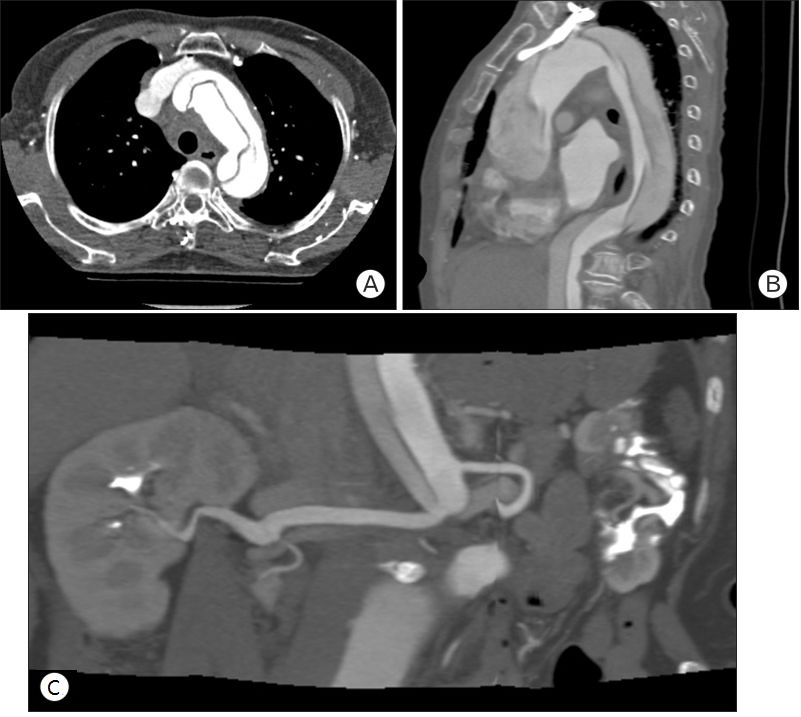

患者女性,79岁,因胸痛、乏力、言语障碍到当地医院急诊就诊,由于心电图、心肌酶正常,胸片显示纵膈轻度增宽,医生疑诊为主动脉夹层。CT检查显示升主动脉上方有“皮瓣”,纵膈的改变被忽略(图3)。患者被诊断为主动脉夹层,收入ICU住院治疗,住院期间患者胸痛有所缓解,但变得虚弱并有咽痛、吞咽问题。

图3 当地医院的影像学检查(右上图白色箭头:纵膈内的浸润灶及液性暗区,短黑箭头:气管,短长箭头:食道;右下图箭头:误诊为主动脉夹层中的内膜瓣)

发病5天后患者被转入上级医院,追问病史发现患者入院前有发热和“感冒”。咽喉检查发现右侧扁桃体肿大,有脓液排出,颈部检查未见明显肿胀或压痛。血液检查显示白细胞增多和高C反应蛋白(290 mg/L),血气显示低氧血症(PO2 67 mmHg),胸片纵膈明显增宽。

再次行CT扫描颈部和胸部,发现右侧扁桃体软组织肿胀,扁桃体周围和咽后间隙多发脓肿并向下延伸至上纵膈(图4)。考虑诊断纵膈炎、脓肿形成,立即插入胸管引流并急诊开胸手术。最终,患者因脓毒症导致多脏器衰竭,在入院第20天死亡。

图4 发病5天后CT(右上图白色箭头:气管周围多个脓肿,短黑箭头:气管,黑长箭头:上腔静脉;右下图白色箭头:脓肿沿降主动脉向下延伸)